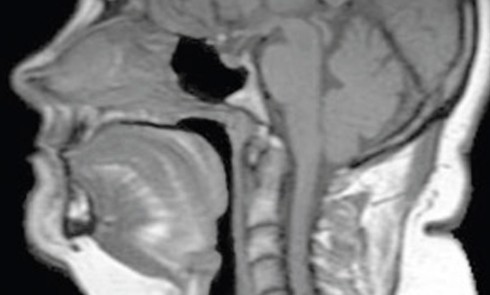

Certains troubles du sommeil, en particulier le trouble insomnie et le Syndrome d’apnées et hypopnées obstructives du sommeil (Sahos), établissent...Une introduction complémentaire à la médecine dentaire du sommeil

La discipline odontologique « médecine dentaire du sommeil » est résolument pluridisciplinaire et elle exige des professionnels impliqués un important savoir-faire médical,...Le Sahos : définition, épidémiologie, physiopathologie, conséquences

Le Syndrome d’apnées et hypopnées obstructives du sommeil (Sahos) est une pathologie chronique, fréquente dans la population générale d’âge moyen,...Le Sahos et le chirurgien-dentiste : dépistage au quotidien

Le Syndrome d’apnées hypopnées obstructives du sommeil (Sahos) est caractérisé par des épisodes récurrents d’obstruction complète (apnée) ou partielle (hypopnée)...Syndrome d’apnées-hypopnées obstructives du sommeil : spécificités chez l’enfant